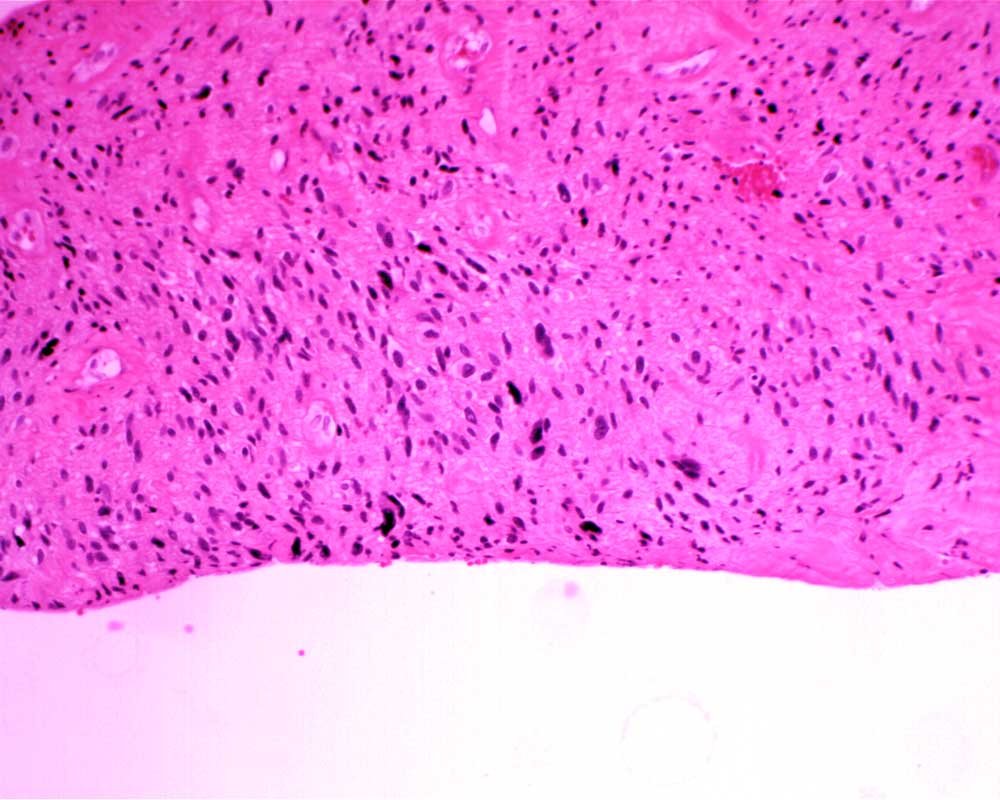

Case: ThighMass2

Final Diagnosis: